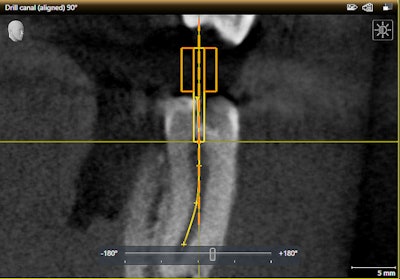

Dentsply Sirona launches new 3D endo software

Dentsply Sirona is launching a new 3D-guided endodontic treatment planning software at CDA Presents 2018 in Anaheim.

The Sicat Endo software is optimized for both 2D and 3D imaging devices. The software offers easy identification of all root canals in 3D and exact determination of working length and cavity access depth, according to Dentsply Sirona.

See the software at booth No. 1302.